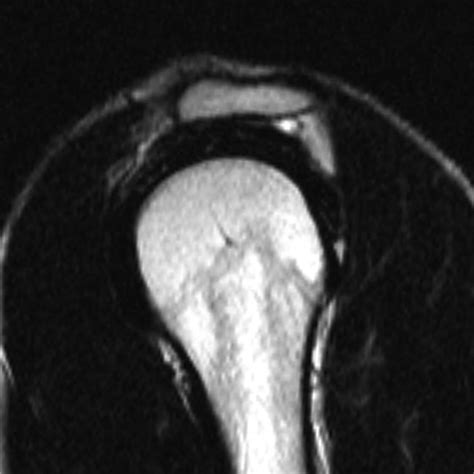

The morphology of the acromion was famously classified by Bigliani into three distinct shapes, based on its curvature when viewed from the side (on an MRI or X-ray scan). This classification is crucial for understanding how the bone interacts with the soft tissues beneath it.

• Type II (Curved): The under-surface is curved, following the contour of the humeral head. This shape significantly reduces the subacromial space compared to a Type I acromion.

MRI scans are the gold standard for visualizing both the acromion shape and the condition of the soft tissues (tendons and bursa). An MRI will clarify whether the Type II structure is simply present or if it is actively causing damage to the rotator cuff. X-rays are also commonly used, specifically a supraspinatus outlet view, which allows the radiologist to clearly visualize the curvature of the acromion.